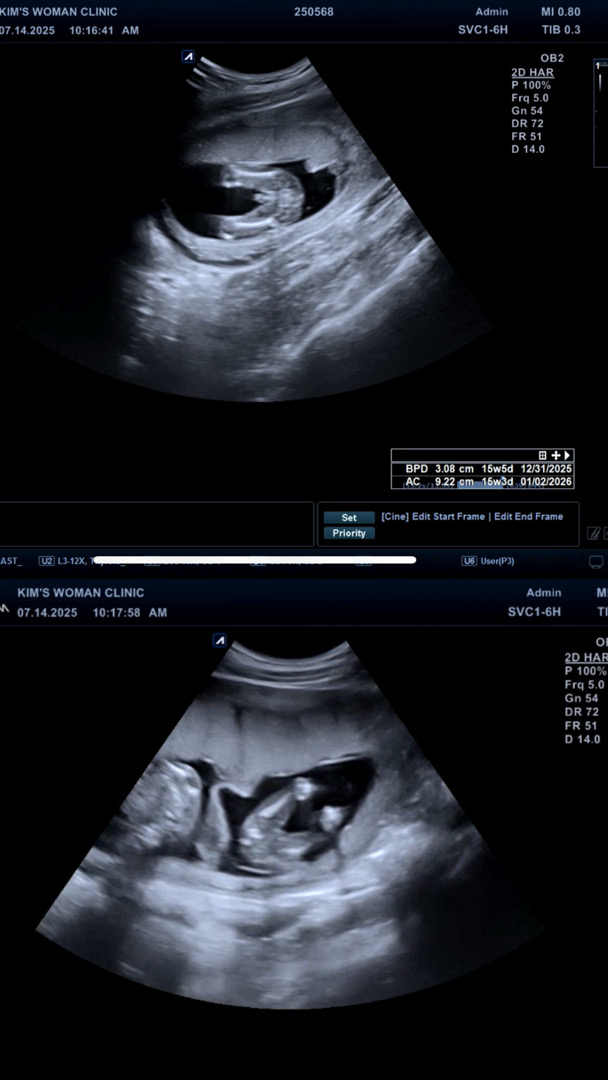

15주차 쌍둥이 초음파에요!

아들 딸 맞는거 같죠..?

위에 아들 아래 딸 맞는거같아여ㅎㅎ